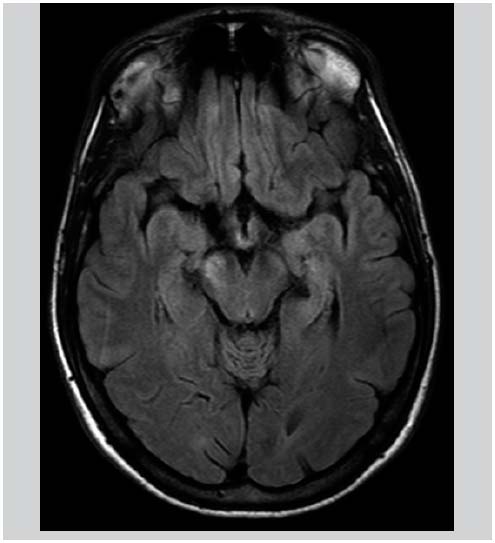

L’atteinte des vaisseaux de la rétine est appelée vascularite rétinienne.

Celle des zones antérieure et/ou postérieure de l’œil est nommée uvéite.

Maladie De Behçet Peut On En Mourir Oeil Et Maladie de Behçet

Maladie De Behçet Peut On En Mourir Dr Eleonore Diwo - Uvéite